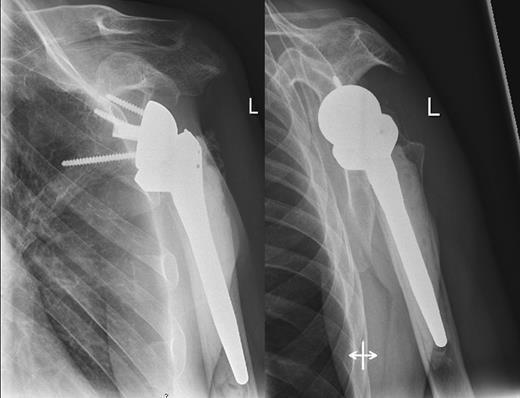

A 48-year-old patient was referred to a level I trauma center after the first incidence of an epileptic convulsion. The patient was alert and oriented with retrograde amnesia from the time of convulsion. Peripheral neurology was normal. The X-rays showed bilateral posterior shoulder dislocation with fractures of both humeral heads (Fig. 1). A CT of the head and both shoulders was performed to exclude intracerebral pathology and to achieve better demonstration of the shoulder fractures (Fig. 2). According to the AO fracture classification, he had a 11-C3.1 fracture on the left side and a 11-C3.3 fracture on the right side. The right side fracture was treated with a cementless hemiarthroplasty (OrTra®, Zimmer, Germany), while an open reduction and internal fixation (ORIF) with an angular stable plate (Philos®, Synthes, Germany) was performed on the left. Despite the high incidence for humeral head necrosis after ORIF in this fracture type, this option was chosen based on the young age of the patient. Postoperative X-rays and CT showed adequate positions of the implants (Fig. 3). The shoulders were immobilized in Gilchrist bandages followed by passive mobilization for the first 6 weeks by physiotherapy with a limitation for abduction and anteversion to 90°. There were no complications intraoperatively or in the first postoperative time. Patient was discharged after 8 days. Antiepileptic therapy was initiated with 5 mg clobazam and subsequent increasing doses over the following weeks. There were no more signs of epilepsy in the follow-up. A CT 4 months after operation showed dislocation of a fragment on the left side which was subsequently resected. At the 1-year postoperative review, the patient showed impingement of the left shoulder with abduction limited to 50° by both the plate and an osteophyte. Radiological assessment revealed signs of necrosis of the head. The plate was removed and the osteophyte resected. Eighteen months after injury, the left shoulder showed progressive avascular osetonecrosis of the head (Fig. 4) and after plate removal an inversed prosthetic replacement had to be performed (Fig. 5). At the last follow-up 3 years after injury, the patient was free of pain with a bilateral range of motion of 90° abduction and elevation.

Avascular head necrosis over the following one and a half years on the left side with ongoing necrosis after plate removal.